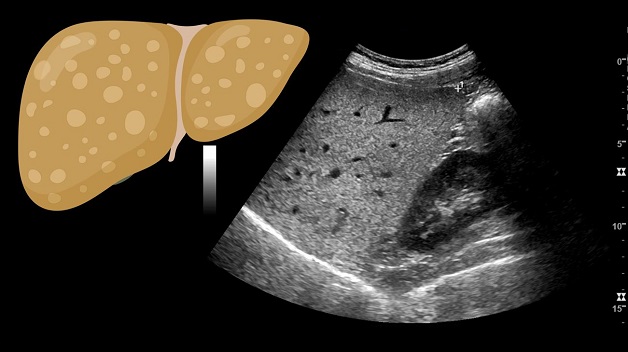

2. Hình ảnh của gan nhiễm mỡ trên siêu âm

Bệnh gan nhiễm mỡ được phát hiện trên siêu âm chủ yếu dựa vào các triệu chứng như tăng độ sáng tại các vùng khác nhau của gan hoặc tăng độ sáng của mô gan khiến cho đường bờ của các cấu trúc mạch máu bị mờ đi.Trên hình ảnh siêu âm, hình thái gan sẽ xuất hiện những đốm sáng rải rác hoặc tập trung thành từng khu. Tình trạng này sẽ có sự khác nhau tùy theo mức độ nhiễm mỡ gan ở từng người. Khi gan bị nhiễm mỡ, bác sĩ siêu âm sẽ không nhìn thấy hoặc thấy không rõ hệ thống mạch bên ngoài trên gan.Bên cạnh đó, độ hồi âm của gan bình thường bằng hoặc tăng nhẹ so với vỏ thận hoặc lách. Khi gan bị nhiễm mỡ, hồi âm của gan sẽ vượt trội so với vỏ thận và lách, đồng thời có sự suy giảm của sóng siêu âm, mất sự rõ nét của cơ hoành và phân định nghèo nàn các cấu trúc trong gan.

3.Đánh giá mức độ gan nhiễm mỡ trên siêu âm gan nhiễm mỡ

Bác sĩ có thể đánh giá mức độ gan nhiễm mỡ dựa vào hiện tượng tăng độ sáng của nhu mô gan trên hình ảnh siêu âm gan như sau:

+ Mức độ 1:

Gan tăng âm nhẹ, mức độ hút âm chưa có sự thay đổi đáng kể, vẫn còn xác định được cơ hoành và đường bờ các tĩnh mạch trong gan.

+ Mức độ 2:

gia tăng sự lan tỏa độ hồi âm và hút âm, khả năng xác định được bờ các tĩnh mạch trong gan và cơ hoành đã giảm đi nhiều.

+ Mức độ 3:

gia tăng rõ rệt mức độ hồi âm và hút âm, không còn nhận diện được đường bờ các tĩnh mạch trong gan, cơ hoành, một phần nhu mô gan ở phân thùy sau gan phải trên mặt cắt dưới sườn.